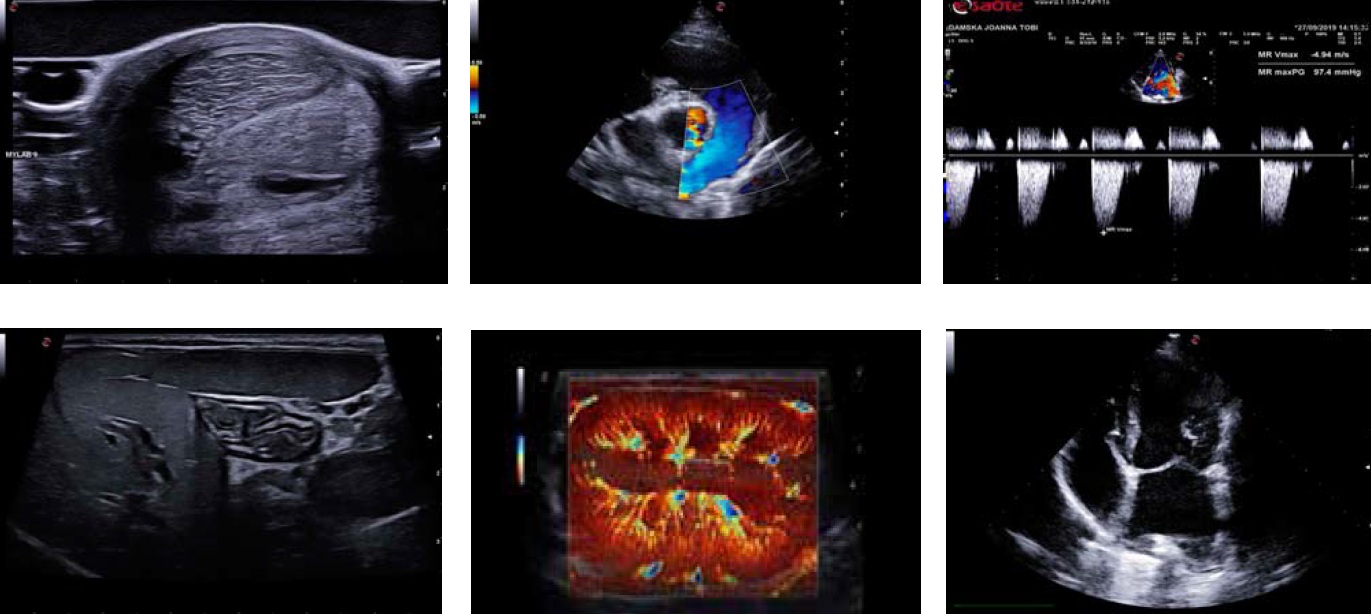

Клінічні ультразвукові зображення, отримані на апараті MyLab Sigma VET. Приклади включають: зображення органу в В-режимі, ехокардіограма, спектральний доплер, зображення з використанням розширених режимів